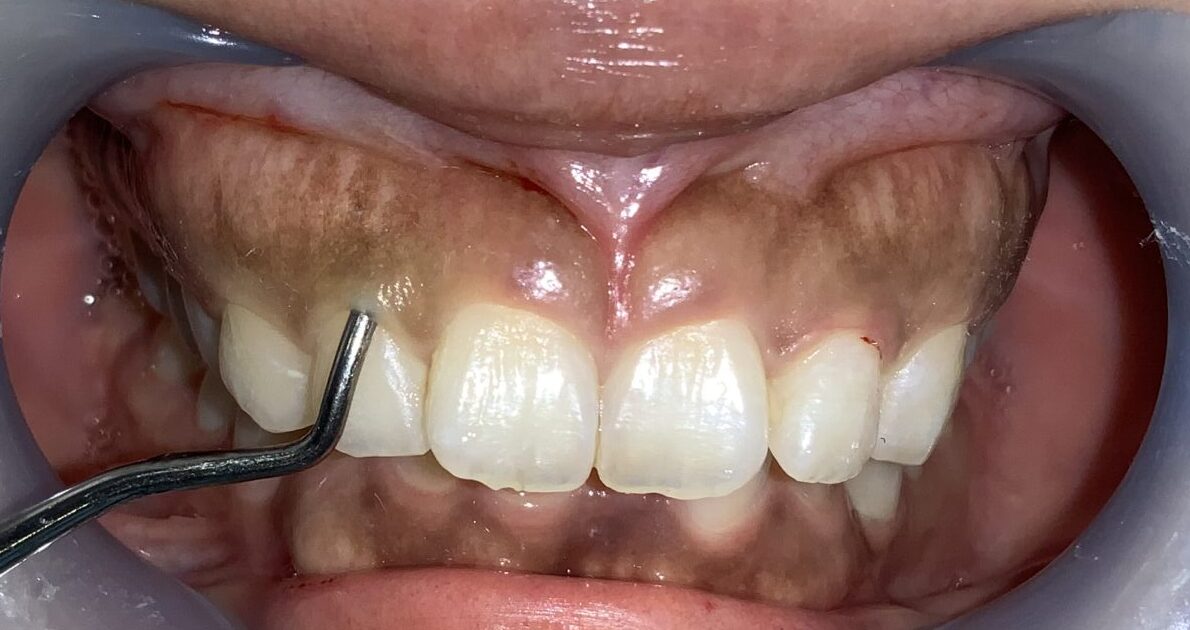

上の歯が下の歯を覆い被せてしまい、下の歯が全く見えない状態を過蓋咬合(かがいこうごう)と言います。

このような患者様は歯が歯ぐきに潜り込んでいる場合が多く、同時に歯槽骨が尖っていたり、ざらざらしていたり、歯槽骨までが歯を覆い被せていたりする場合がありますから、歯冠長延長術と同時に歯槽骨整形も一緒にしなければ、後戻りをしたり、綺麗に仕上がらない場合があります。

反対側の前歯です。

こちらもたくさんかぶっています。歯槽骨のとがった部分もあり、ざらざらした面もありますから、歯槽骨整形も同時に行う必要がありそうです。